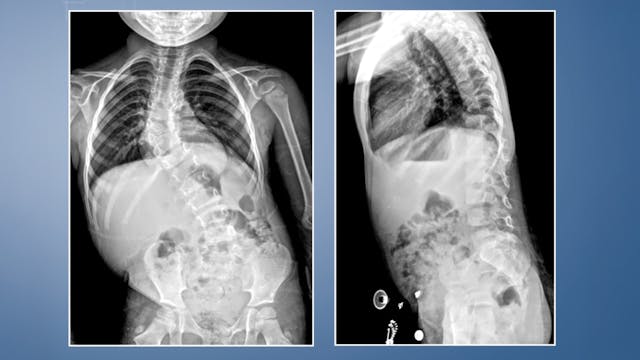

Adolescent idiopathic thoracolumbar scoliosis

The learning objectives are 1. The indication for surgical treatment of a thoracolumbar adolescent idiopathic scoliosis with curve progression.

2. The applic...